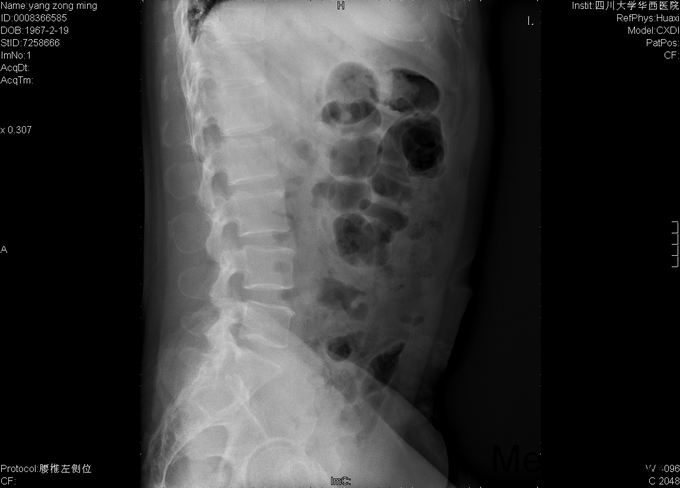

男,48岁8月,因“腰部疼痛伴右腿疼痛1+月”入院。患者1+月前出现腰部疼痛,伴右侧臀部、大腿后部、足背疼痛,大腿后部为主,不影响行走,不伴行走不稳、下肢麻木等,于外院行理疗、针灸等保守治疗,症状未见明显缓解。后症状有所加重,变换体位时疼痛加重,开始出现夜间痛醒,行走困难,遂至当地医院行靶点射频、封闭等治疗(具体不详),效果不佳,于2015-9-28入我院疼痛科,给予对症治疗(具体不详),症状有所缓解,现为进一步治疗入我科。

专科情况:视:双下肢等长,皮肤黏膜完整,无破损,双下肢肌肉无萎缩,脊柱外形正常。触:腰5-骶1棘突间压痛,腰部VAS疼痛评分5分,右下肢VAS疼痛评分6分,右下肢针刺觉减退。动量:四肢肌力、肌张力正常。右侧直腿抬高试验(+),加强实验(+),加强实验(-),双侧髌骨研磨试验(-)。生理反射均正常引出,病理征阴性。辅助检查:2015-9-29数字化X光腰骶椎正侧位摄影示:腰骶退行性病变、骨质疏松。数字化X光胸部正侧位摄影示:心肺未见明显异常。CT椎体一个部位骨三维成像扫描示:1、腰椎退行性病变,L5/S1椎间盘稍向右后突出2、骶管囊肿。MRI腰椎普通扫描示:1、L5/S1椎间盘突出2、腰椎退行性病变。

初步诊断:1、腰5骶1椎间盘突出症;2、骶管囊肿;3、骨质疏松。经皮内镜右侧椎间孔入路腰5骶1椎管减压+椎间盘髓核摘除+射频成形术